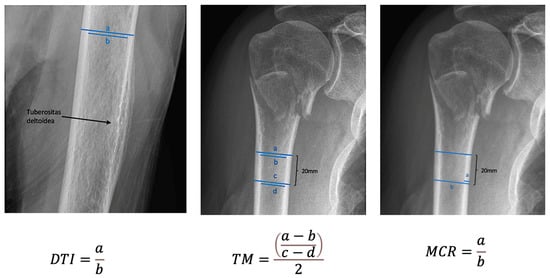

| DTI | 1.4 | 1.2–1.9 | 0.1 |

| TM | 6.2 | 3.1–13.5 | 1.6 |

| MCR | 0.2 | 0.1–0.3 | 0.03 |